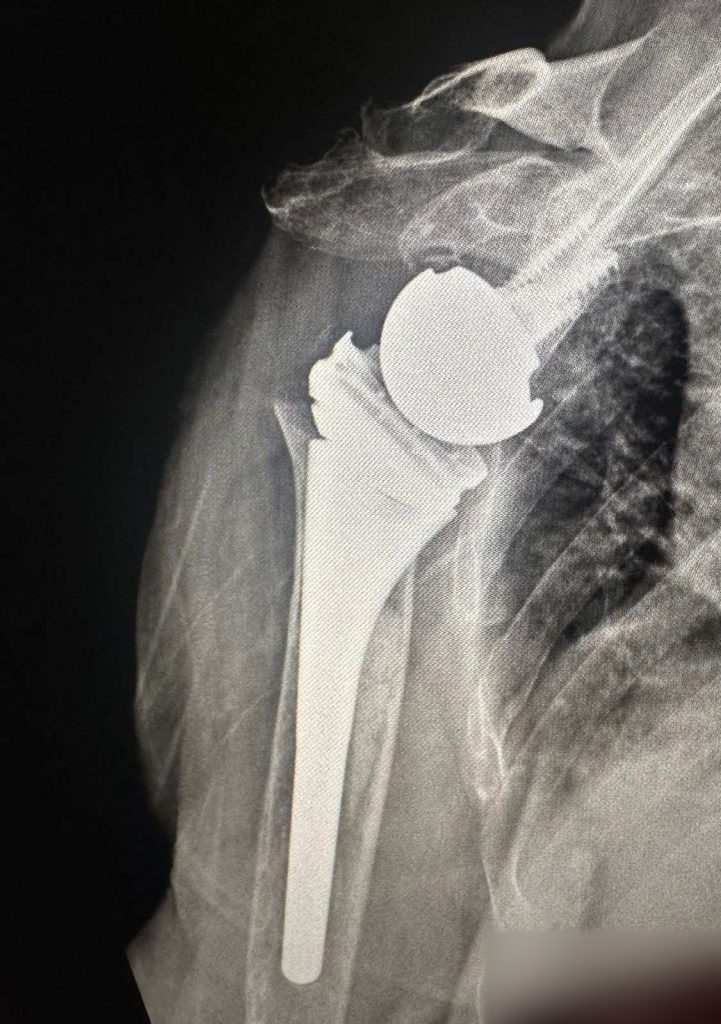

Për herë të parë në Klinikën e Ortopedisë të Qendrës Klinike dhe Universitare të Kosovës janë kryer dy operacione për vendosjen e protezave të supit.

ShSKUK ka njoftuar se ekipi mjekësor në përbërje të dy ortopedëve, si dhe ekipit nga Klinika e Anesteziologjisë dhe stafit infermieror, me sukses të plotë kanë kryer këto dy operacione ortopedike.

“QKUK kishte përfituar si donacion tavolinën operative për ndërhyrje në krahë, nga Klinika me renome botërore Schulthess Klinik, Zvicër”.